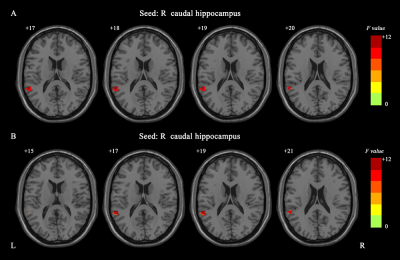

The significant dFC differences among the three groups for the hippocampus seed (voxel p < 0.001, cluster p < 0.05, GRF corrected). The color bar indicates the F values from One-Way ANOVA analyses. dFC, dynamic functional connectivity; GRF, Gaussian random field; L (R), left (right) hemisphere.